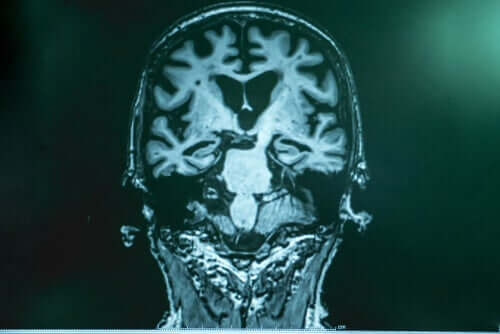

Il Dottor Lopera spiega che in caso di Alzheimer si verifica una sorta di accumulo di “spazzatura” nel cervello. Quest’ultima è composta da una proteina chiamata amiloide. I frammenti della stessa si uniscono e formano una “colla” che aderisce ai neuroni, causando una raffica di errori. L’altra parte della spazzatura è costituita dalla proteina tau, che avvolge il neurone, lo rinchiude e lo uccide. La Tau è la parte più nociva.

Dopo averla sottoposta ad analisi scrupolose a Boston, gli esperti appurarono che il cervello della paziente era pieno di amiloide, persino più che negli altri casi. Nonostante ciò, presentava scarsissimi livelli di tau. Le ricerche permisero di appurare che nella paziente era presente un’altra mutazione che inibiva la produzione della tau e che, quindi, ritardava il decorso della malattia.